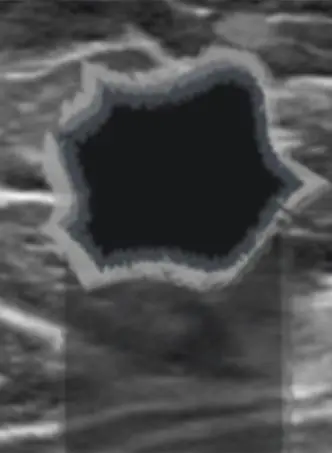

암(Cancer)

저에코성

일반적으로 불규칙한 모양

원형 또는 타원형도 있음

불분명확한 경계, 각형, 미세엽상, 침상경계

수직방향

자주 후방 에코 증강

덩어리 내외부에 작은 석회화 발견